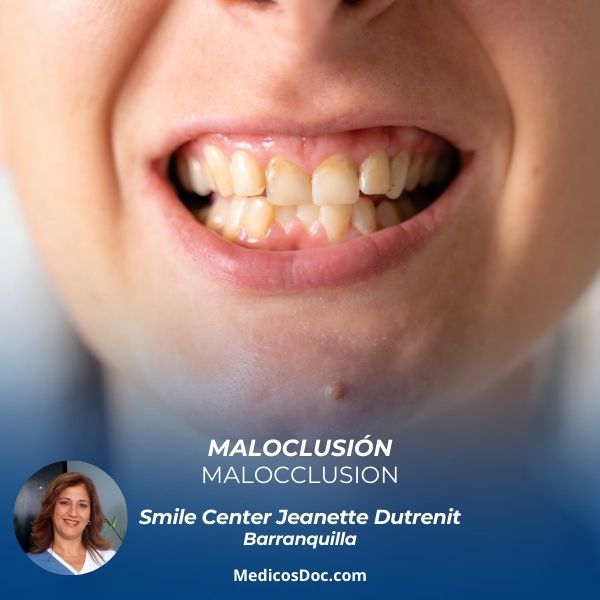

- Manejo clínico de maloclusiones clase I, clase II y clase III ,

Las especialidades de Smile Center Jeanette Dutrenit son: Odontólogo, Odontología estética, Rehabilitación oral, Implantes dentales, Ortopedia maxilar, Periodoncia, Odontopediatra, Endodoncia, Ortodoncia.